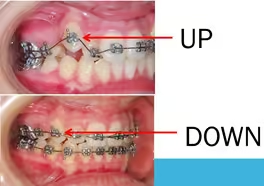

You usually think about your jaw as being solid like a rock, but when you are growing your jaw is really more like clay. If you apply pressure to your jaw, you can get your jaw to stretch, it can get wider, or it can be moved back. Still, the important thing is that when your braces pull on your jaw, the braces change the shape of your jaw. In the same way, if you push on your teeth, your teeth will move around in your mouth. The orthodontist uses that fact that he can apply force to get your jaw and teeth to move, to stretch your mouth so all your teeth fit.

Braces – ‘Look A Little Ugly Today But for Beautiful Tomorrow’